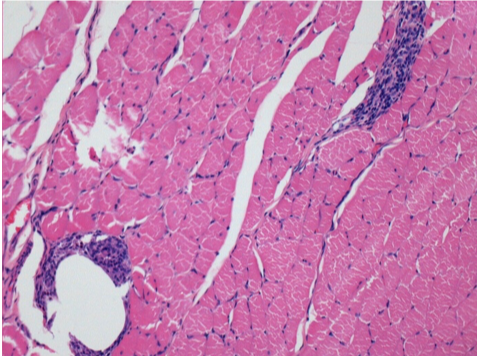

7 months after Endopeel Injection

7 months (D210)after Endopeel IM Injection 0.1ml in the right pretibial muscle.

Complete Restitutio ad integrum after 7 months

L : Control-100xD210

R:100xD210

L :Control 50xD210

R50X-D210